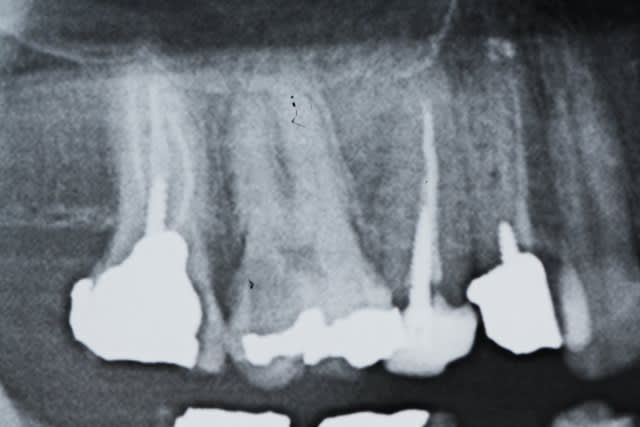

+1 l'interet c'est de faire partager ses astuces. Je ne prétend pas etre le roi de l'endo mais en ce qui me concerne j'ai trouvé une séquence qui me permet d'avoir des résultats reproductibles en un minimum de temps. Une autre 40 mn.

La plus simple lentulo scellement monocone, tuck back à l'apex quand même.